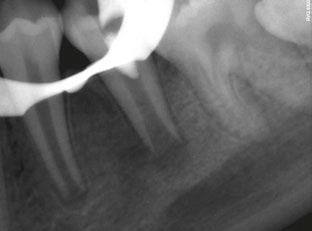

Figure 3 (left): Preoperative CBCT scan of tooth No. 20 showing evidence of a wide open apex. Figure 4 (right): Bleeding noted in the canal immediately after removing the GentleWave platform

In this case report, we present a 10-year-old patient with a wide open apex and a dens evaginatus.5 This case was successfully managed with single visit regenerative endodontics using the GentleWave® System (Sonendo®).6 The outcomes demonstrate not only the feasibility but also the efficacy of this approach in achieving favorable clinical and radiographic results in pediatric patients.

A 10-year-old female patient with a history of swelling and pain associated with tooth No. 20 was referred to our office. The patient exhibited severe dental anxiety. Upon clinical evaluation, a dens evaginatus was noted on the occlusal surface of the tooth (Figure 1). The tooth was sensitive to percussion, palpation, and bite stick while cold testing yielded no response. A periapical radiograph and CBCT scan (Carestream 9600) revealed a wide open apex and evidence of apical periodontitis, leading to the

Figure 1 (left): Dens evaginatus noted on the occlusal surface. Figure 2 (right): Preoperative periapical radiograph of tooth No. 20 showing evidence of apical periodontitis and a wide open apex

diagnosis of a necrotic pulp and symptomatic apical periodontitis of tooth No. 20 (Figures 2 and 3).